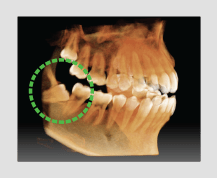

El innovador FOV proporciona un volumen en forma de arco que muestra una vista más amplia de la dentición en comparación con otros dispositivos del mismo FOV.

Normalmente, una imagen de 10x8.5 muestra el diente No.8. Sin embargo, cuando los terceros molares están tumbados sobre su lado hay una gran posibilidad de que el diente se corte de la imagen.

El “volumen en forma de arco” elimina esta posibilidad y muestra el área de dentición oculto.